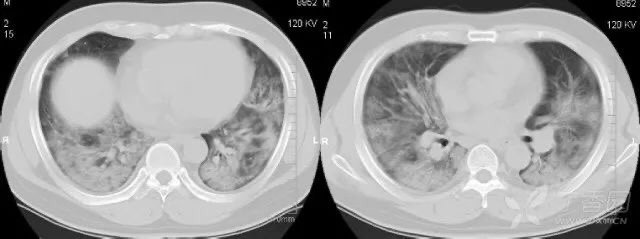

1. 1 病毒性肺炎:男性患者,29 岁,CT 示双肺弥漫性分布的片絮状、磨玻璃样影。

1.2 H1N1 肺炎:CT 显示双肺片絮状、磨玻璃样影呈弥漫性分布。